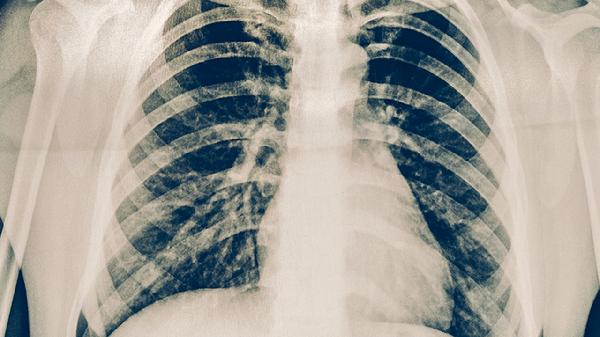

胸部X线检查能发现肺结核的典型影像学表现,如肺上叶尖后段或下叶背段的浸润性病变、空洞形成等。该检查具有辐射量小、费用低的优点,但早期病变或某些特殊类型肺结核可能表现不典型,需要进一步检查确认。

胸部CT检查能更清晰显示肺部病变细节,对早期病变、粟粒性肺结核及合并症的诊断价值较高。高分辨率CT可发现微小病灶,增强CT有助于鉴别诊断。但CT检查费用较高且辐射量相对较大,通常不作为常规筛查手段。